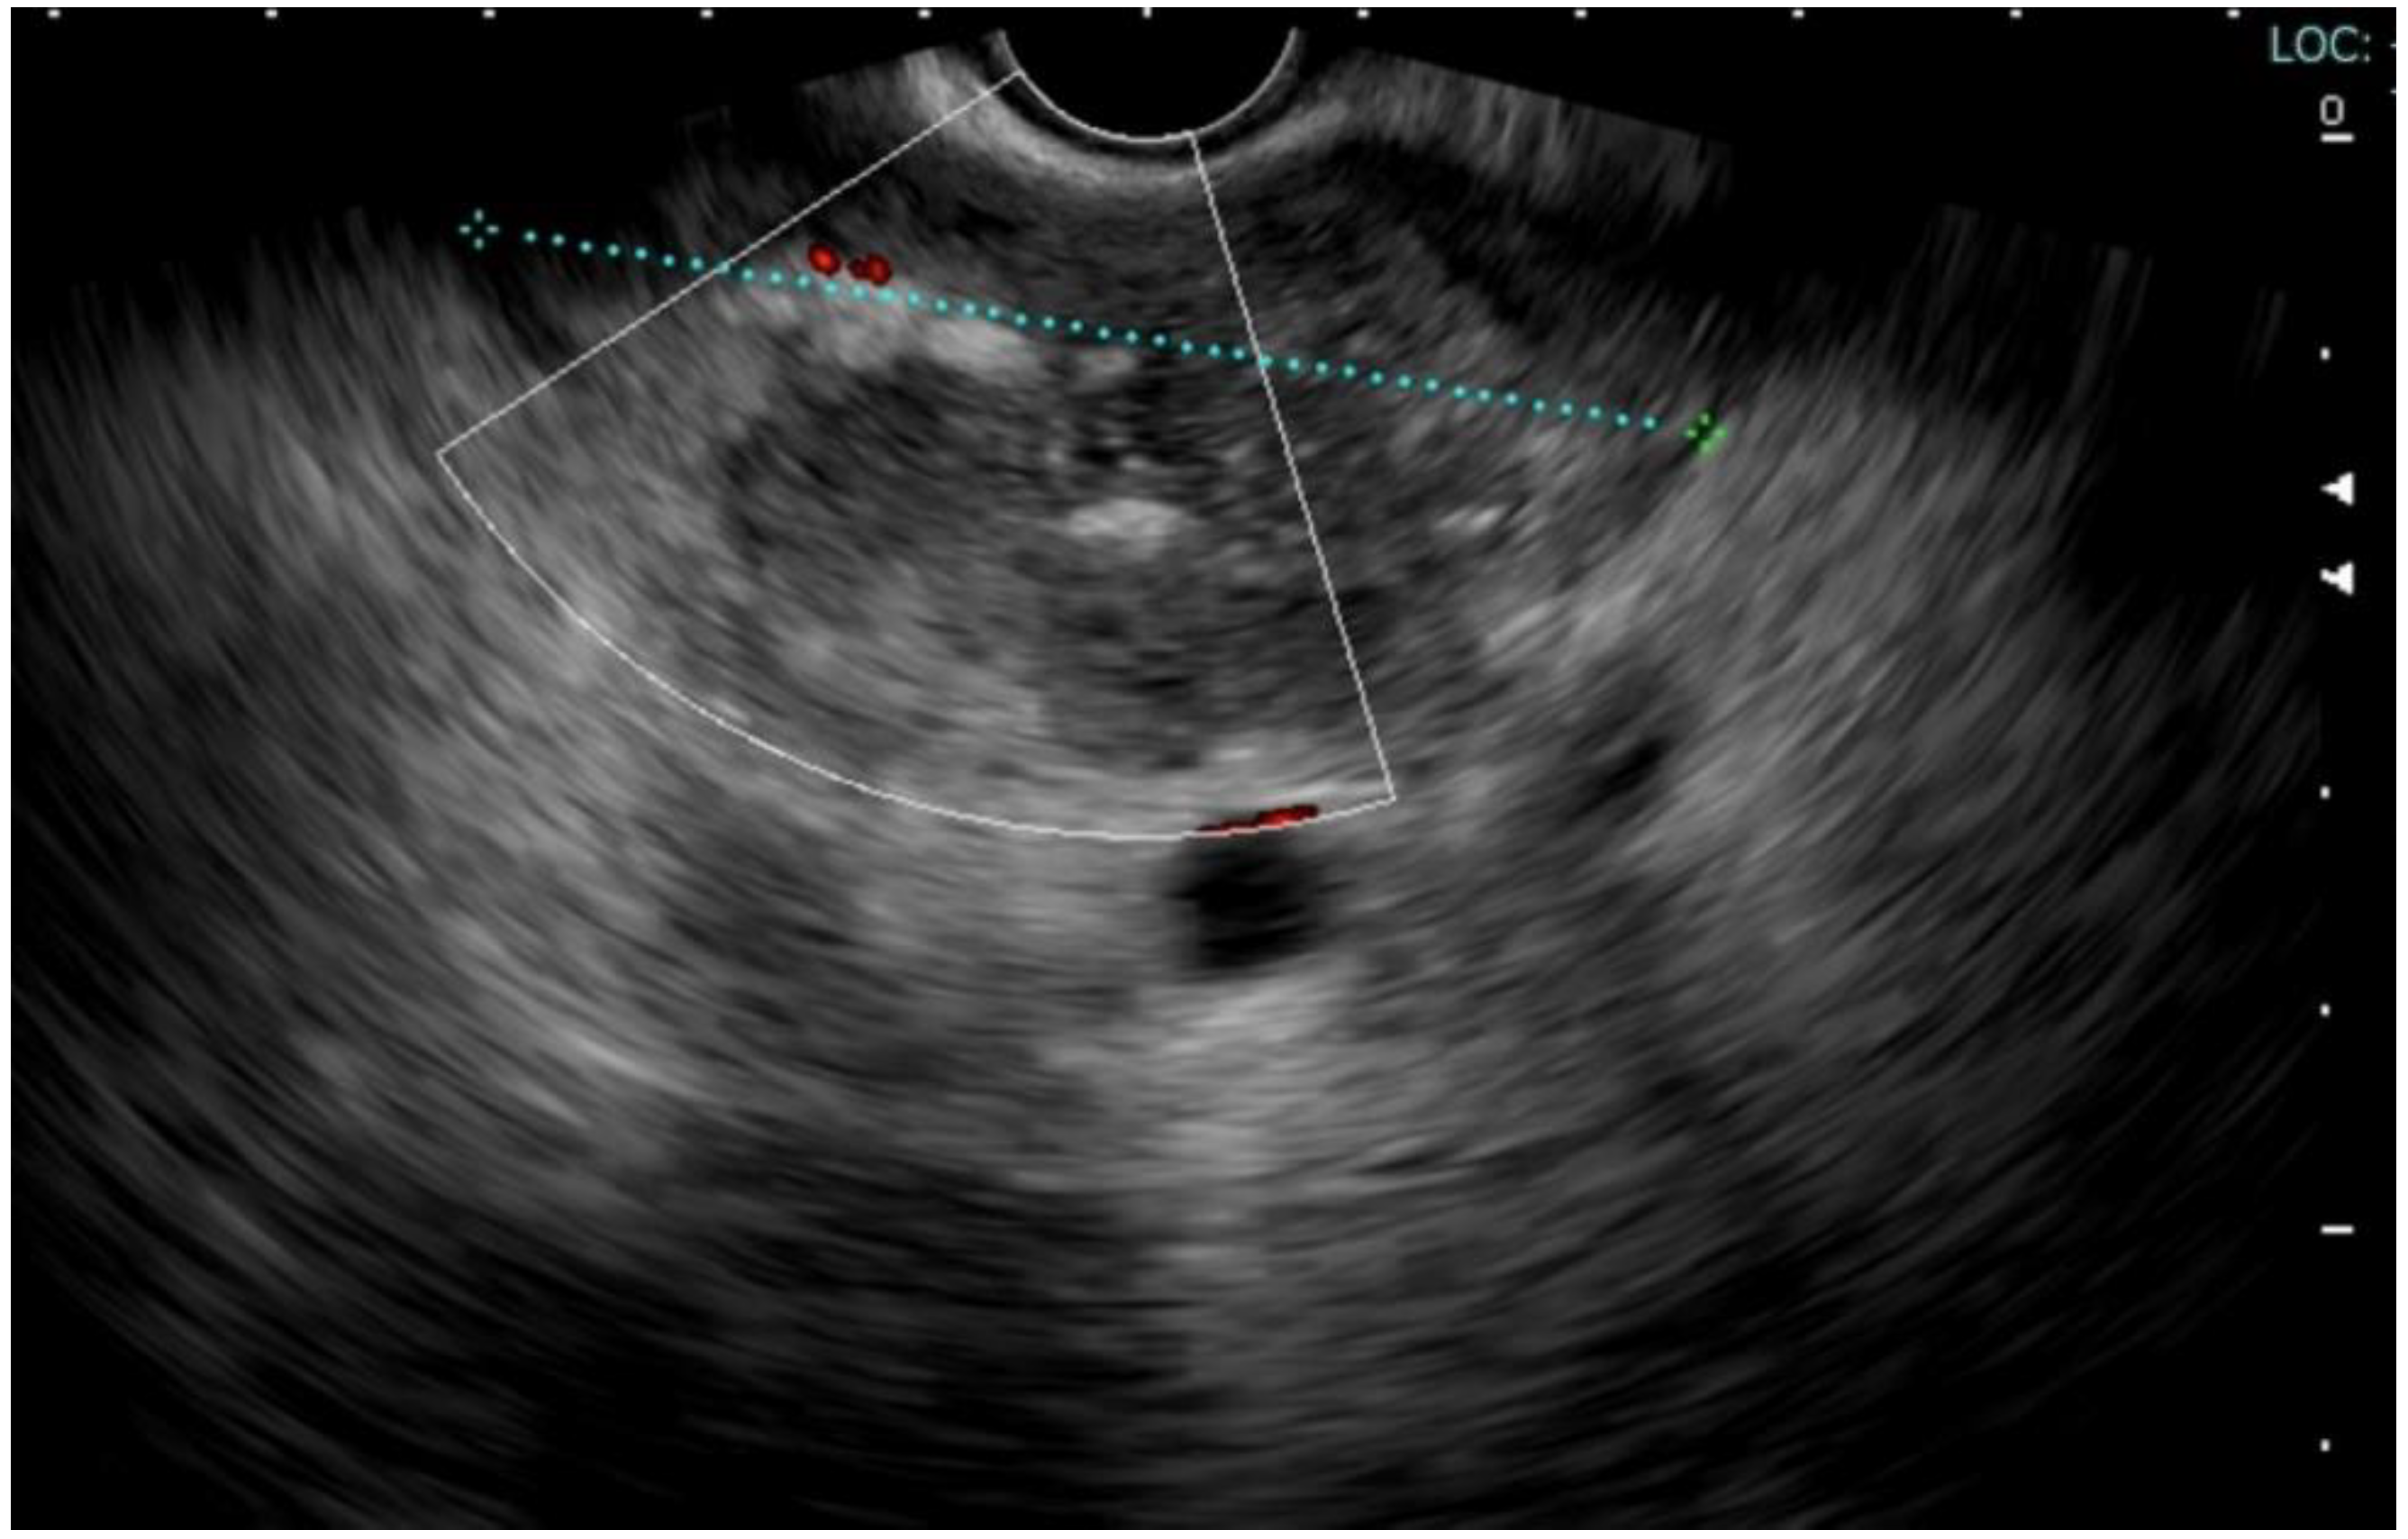

2. Case Report